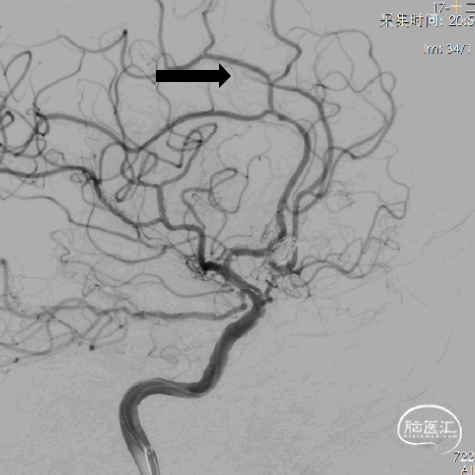

12、超选左侧大脑前动脉跟进微管,可见路径迂曲。

13、支架置入后左侧大脑前动脉血流好转。

14、栓塞后造影。